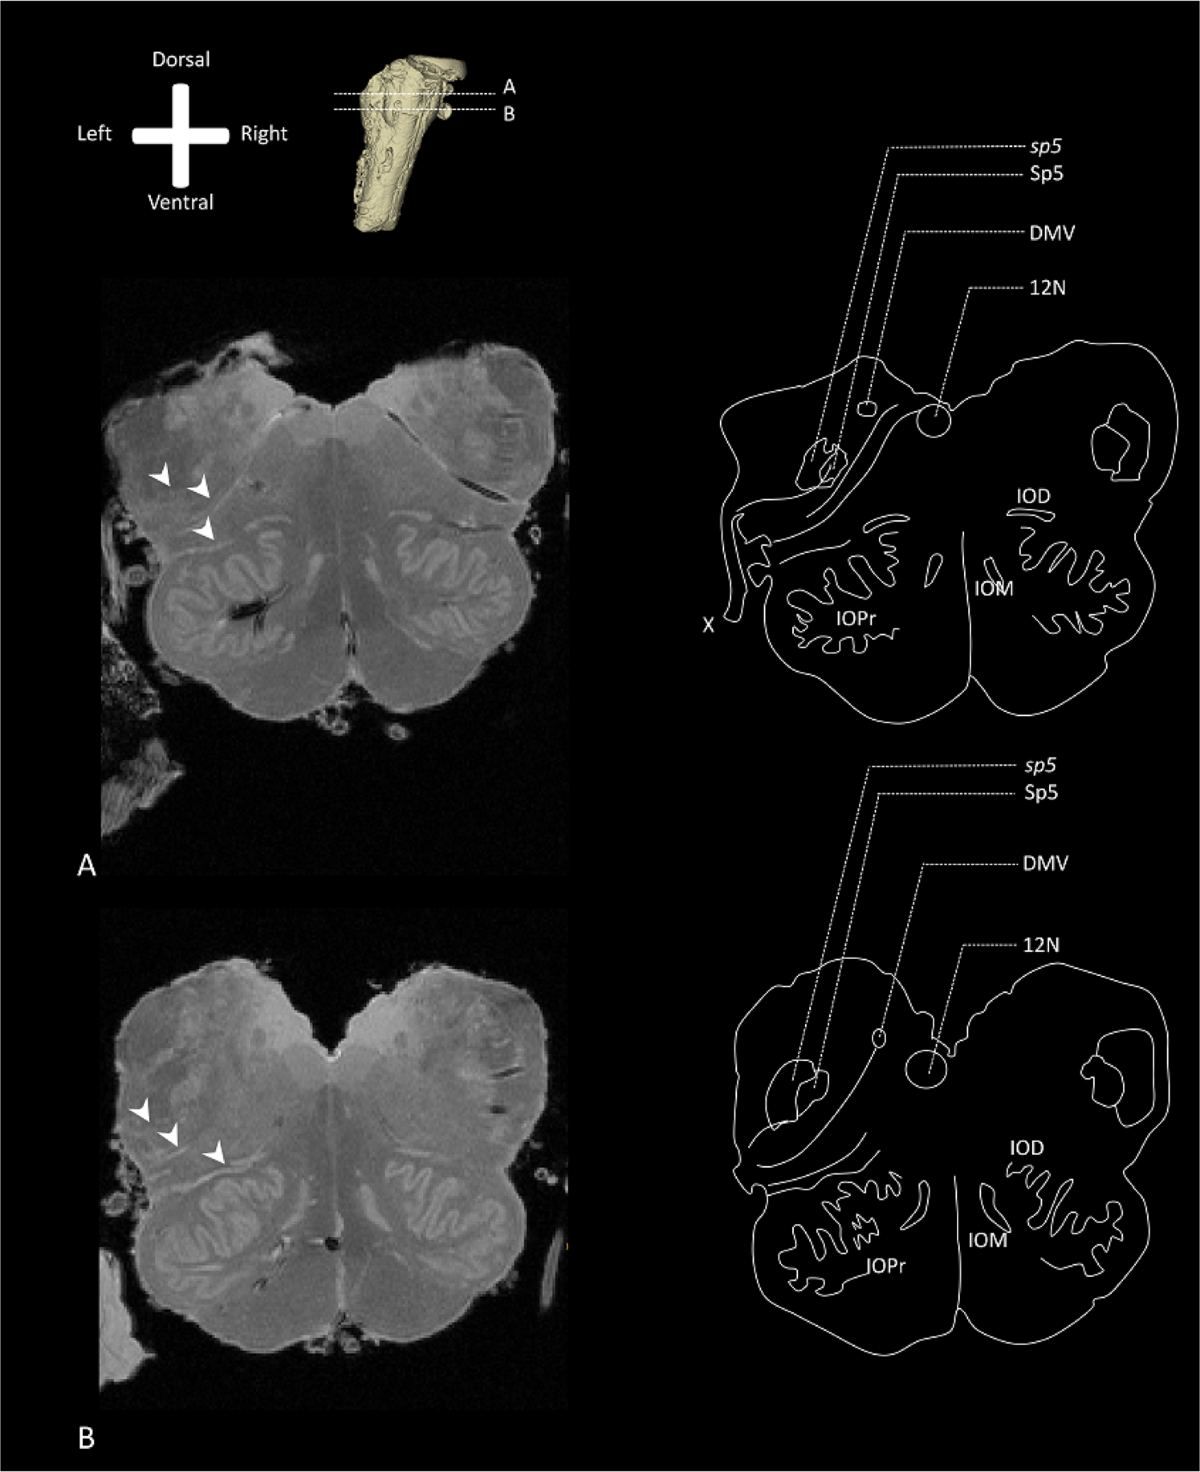

Trigeminal Nucleus Mri